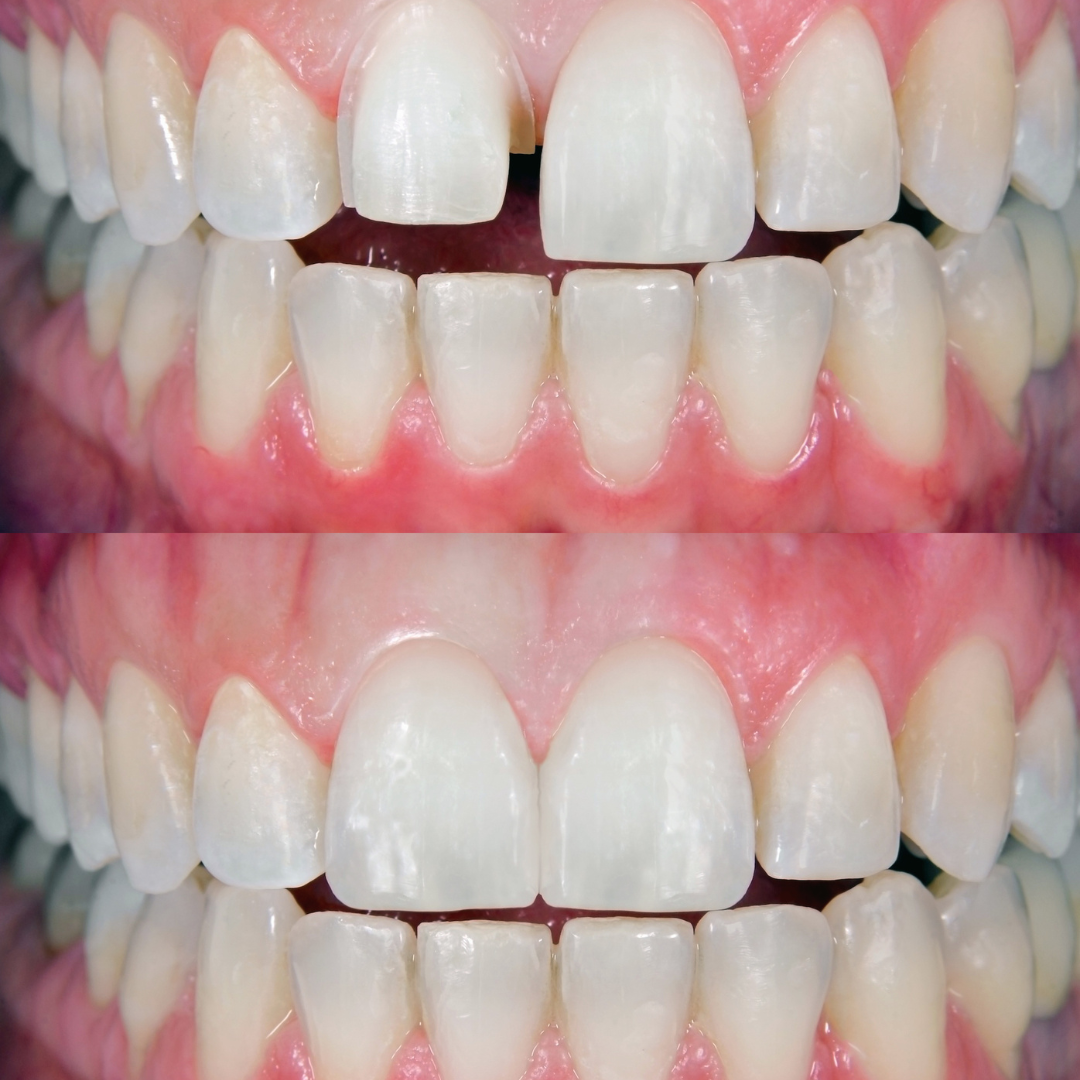

বন্ডিং ট্রিটমেন্ট একটি দাঁতের পুনর্গঠন প্রক্রিয়া!

যা বিশেষ টুথ-কালার রেজিন ব্যবহার করে দাঁতের ফাটল, ক্ষয়, চিপ বা রঙ পরিবর্তন মেরামত করে। এটি দাঁতের ফাঁক বন্ধ করতেও সাহায্য করে।